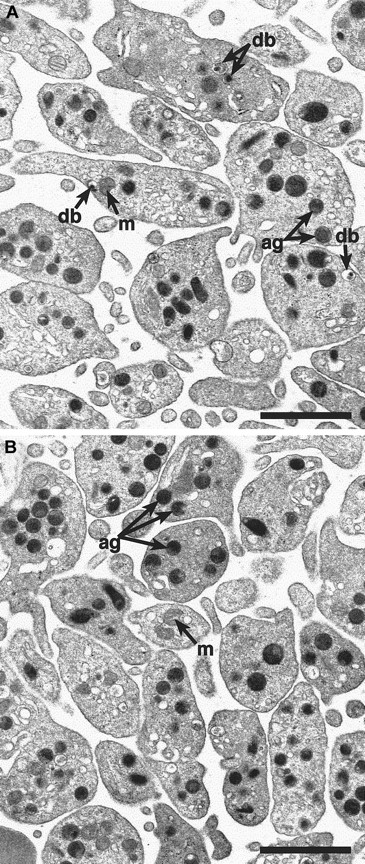

Alpha-granules appear normal in

cno/cno platelets. Transmission electron microscopy reveals a qualitatively normal structure and number of α-granules in cno/cno platelets. Representative photomicrographs showing normal (panel A) and cno/cno (B panel) platelets. m indicates mitochondria; db, dense bodies; ag, α-granules. Bar, 1 μm.